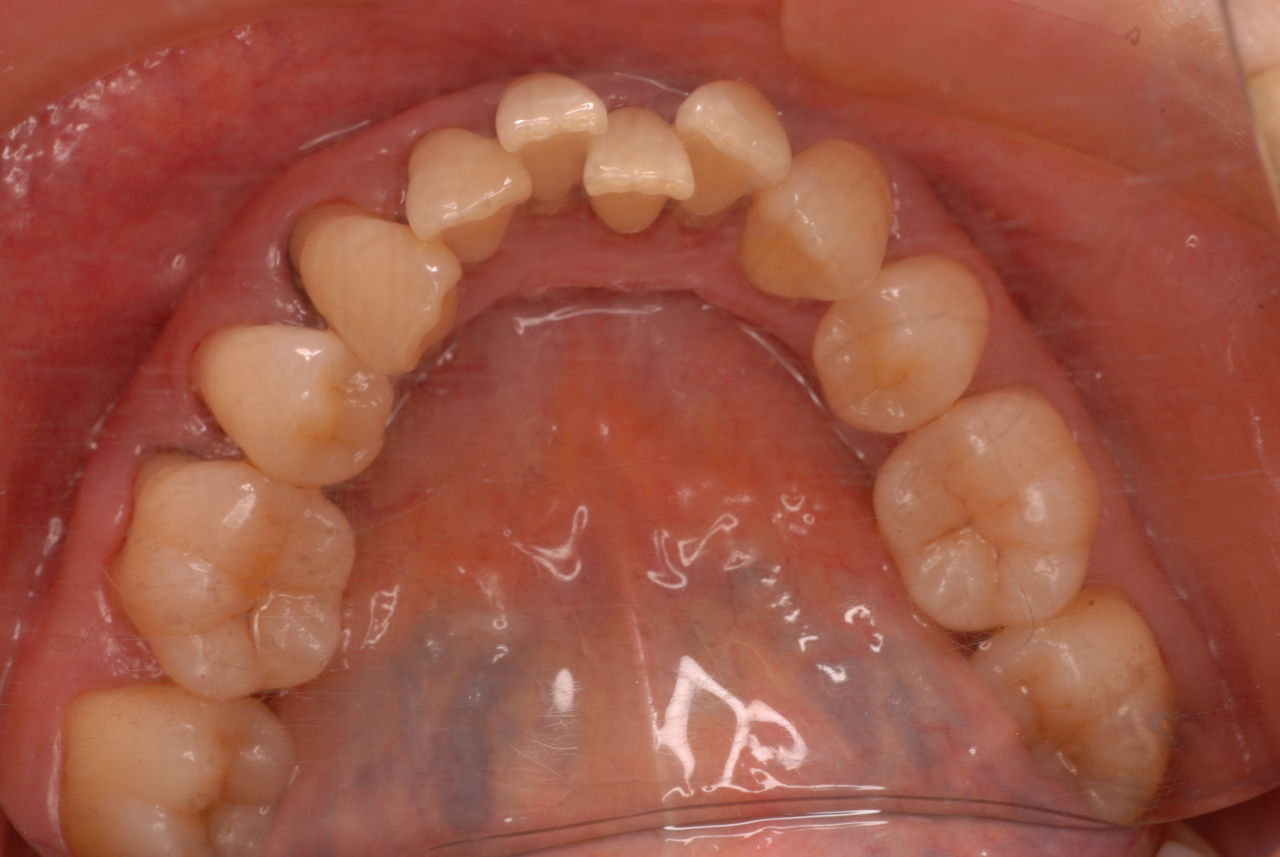

ある方の例です。親不知が痛くなってきました。一見問題ないようです。でも歯周病を常に治療している優れた歯科医師ならば、乾燥させてみた歯茎の色の変化で殆ど歯周病罹患部を指摘できるそうです。

検査をすれば恐ろしいほどの状態だといえるのです。10年後は虫歯と歯周病で残っている歯は何本なのか心配になってきました。